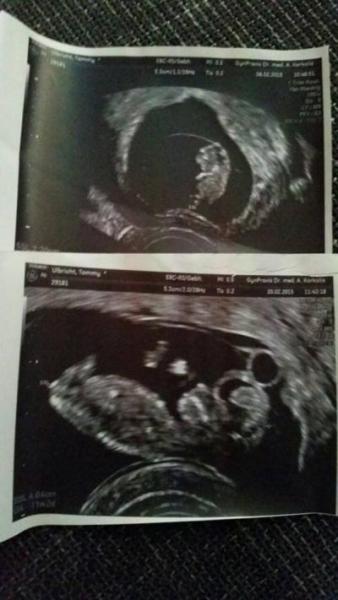

War vorhin beim Frauenarzt. Hatte mich scheinbar völlig verrechnet ich dummbatz. Habe angenommen ich sei in 10+3 Surprise! Bin sogar schon 11+2 Es hat die Kamera weg getreten 4,64cm groß ! :))) LG

Bild zu Stolz wie ein Löwe ! :)))) - Schwanger - wer noch? Rund um die Schwangerschaft